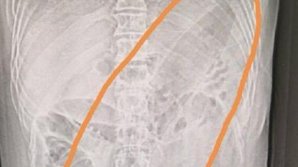

INCREDIBIL! Medicii, șocați când s-au uitat pe radiografia unui pacient: În viața noastră nu am văzut așa ceva (FOTO)